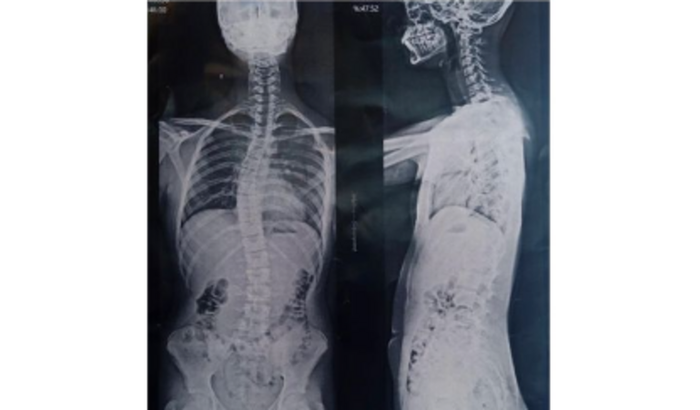

A escoliose idiopática, uma condição médica que causa uma curvatura anormal da coluna vertebral, é um desafio que Miguel tem enfrentado. Mas, em vez de se deixar abater, ele escolheu lutar com um sorriso no rosto e uma determinação inabalável.